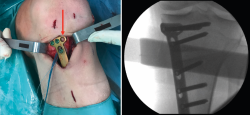

Figura 6. A: colocación de la aguja guía para realizar el túnel tibial; B: brocado del túnel tibial. Se observa el espacio metafisario suficiente para realizar el túnel tibial, sin interferencias con la osteotomía.

Posteriormente, bajo control radioscópico, se realiza la osteotomía apoyando la sierra por debajo de la aguja guía, llegando hasta 1 cm de la cortical lateral. Se introducen los escoplos para abrir la osteotomía (Figura 4). El primer escoplo, el más ancho, se introduce primero para comprobar el corte completo de la cortical posterior. Seguidamente, se coloca el medidor del ángulo de apertura (Figura 5A) y, a continuación, se introduce el distractor en la parte posterior de la osteotomía, evitando así un aumento de la PTP (Figura 5B). En este momento, se puede introducir en la apertura de la osteotomía el aloinjerto o sustituto óseo. Los autores utilizan aloinjerto óseo cuando la apertura es mayor de 10°. Antes de colocar y fijar la placa de osteotomía, se realiza el túnel tibial utilizando las herramientas artroscópicas clásicas (Figuras 6A y 6B). Al realizar una osteotomía biplanar, el corte es suficientemente distal como para permitir brocar el túnel tibial de la RLCA sin dificultades.